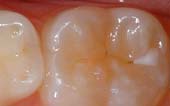

Seal Out Decay

A sealant is a protective coating that is applied to the chewing surfaces (grooves) of the back teeth (premolars and molars), where four out of five cavities in children are found. This sealant acts as a barrier to food, plaque and acid, thus protecting the decay-prone areas of the teeth.

Before

Sealant Applied

After Sealant

Applied